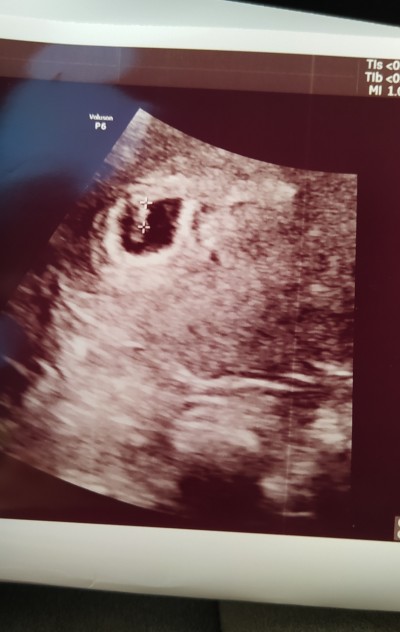

13 haftalık ultrason görüntüsü sizce kız mı erkek mi tahmini olan yazabilir misiniz

Kiz canim hayirlisi olsun ❣

Evet gördüm canim kiz diyorum ben ilk bebismi

Kıza benziyor dedi doktor bildiniz☺️

Kıza benziyor dedi doktor